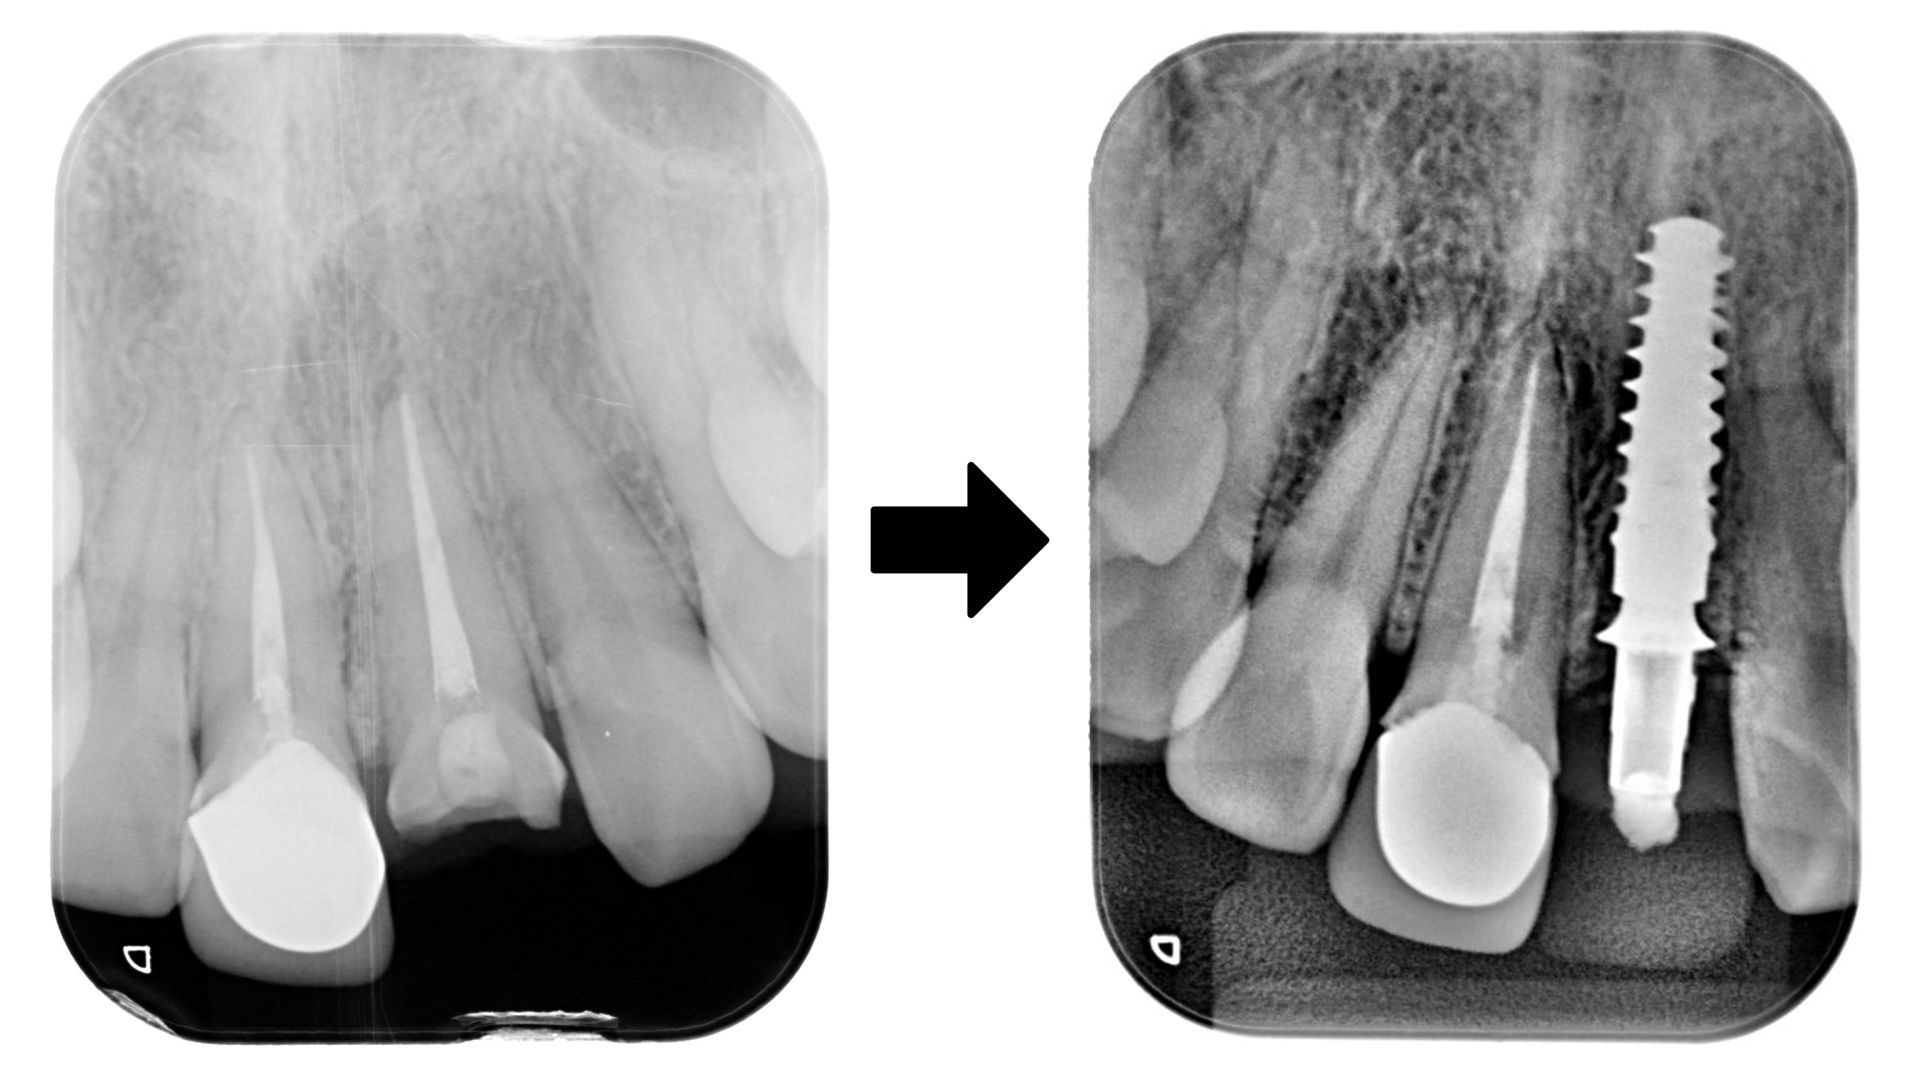

立即植牙—門牙X光片前後紀錄,拔除牙齒並植入人工牙根

手術植入人工牙根,立即裝上臨時固定假牙,快速恢復美觀、減少缺牙空窗期。